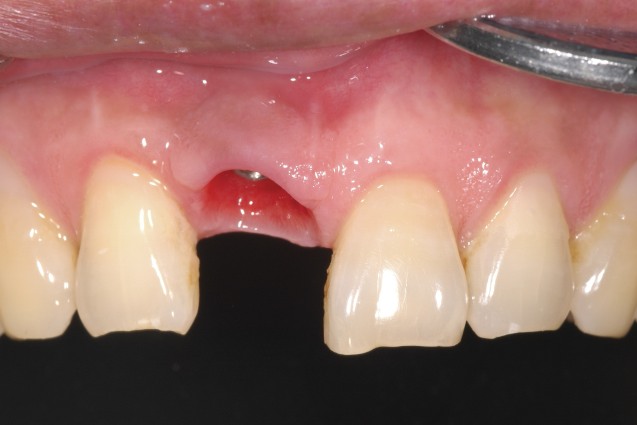

잇몸염증으로 앞니발치해서 특히, 앞니는 보이는 부분이라 많이 상심하실것 같습니다.

1. 잇몸 염증으로 12월 31일 발치했어요 > 발치한 치과에선 뼈가 많이 녹았다며 > 임플란트 무척 어려울꺼라고 브릿지 권합니다 > 브릿지는 옆 치아또한 상하게 해 임플란트 원해요 >

-> 예, 임플란트가 어려운 것은 사실이며, 또한 브릿지가 양옆에 치아를 상하게 하는것도 사실입니다.

->예, 임플란트가 가능합니다. 앞니 임플란트는 어금니에 비해서 시술이 어려우며, 특히 치조골이 흡수된 경우 난이도가 더 어렵습니다. 그래서 임플란트 전문경험이 부족한 선생님들의 경우 브릿지를 권하는 경우도 있습니다.

현재 발치했는지 1주일도 되지않았기때문에 성공적인 앞니 치료를 위해선 시간이 필요합니다. 잇몸이 치유가 다되도록 시간이 필요하며 기간은 엑스레이 진단후 1-3달정도 치유기간이 필요합니다.